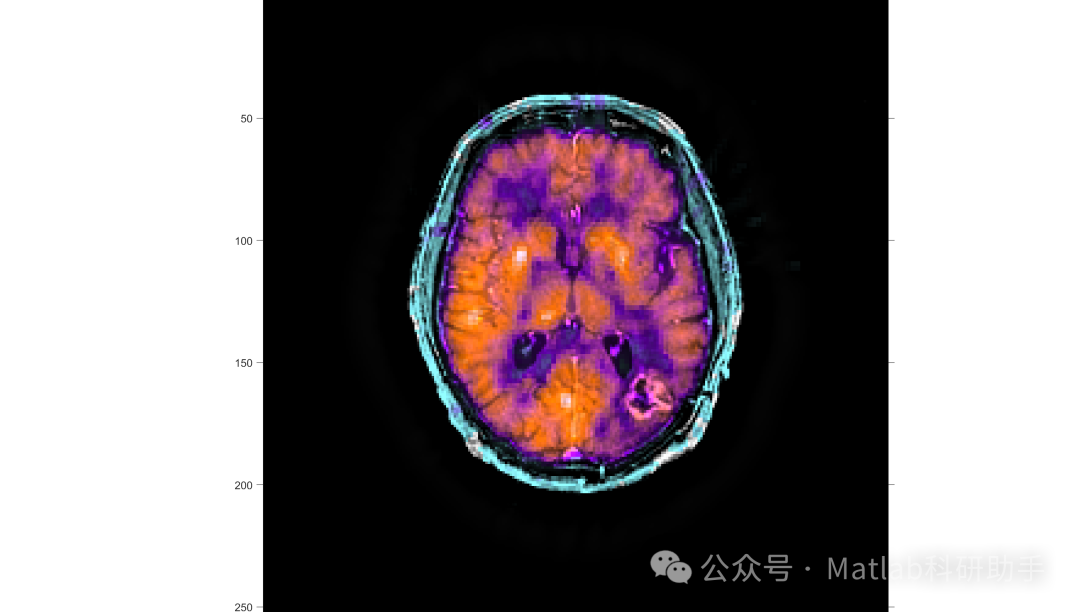

在肿瘤诊疗领域,单一模态医学图像往往存在信息局限性:CT 图像虽能清晰呈现肿瘤的解剖结构与密度差异,但对软组织分辨能力较弱;MRI 图像可精准显示肿瘤与周围神经、血管的软组织关联,却难以提供量化的密度信息;PET 图像能反映肿瘤细胞的代谢活性,助力早期病灶识别,然而空间分辨率较低。多模医学图像融合算法通过像素级、特征级、决策级三级融合架构,将不同模态图像的互补信息有机整合,形成更全面的肿瘤表征数据。

⛳️ 运行结果